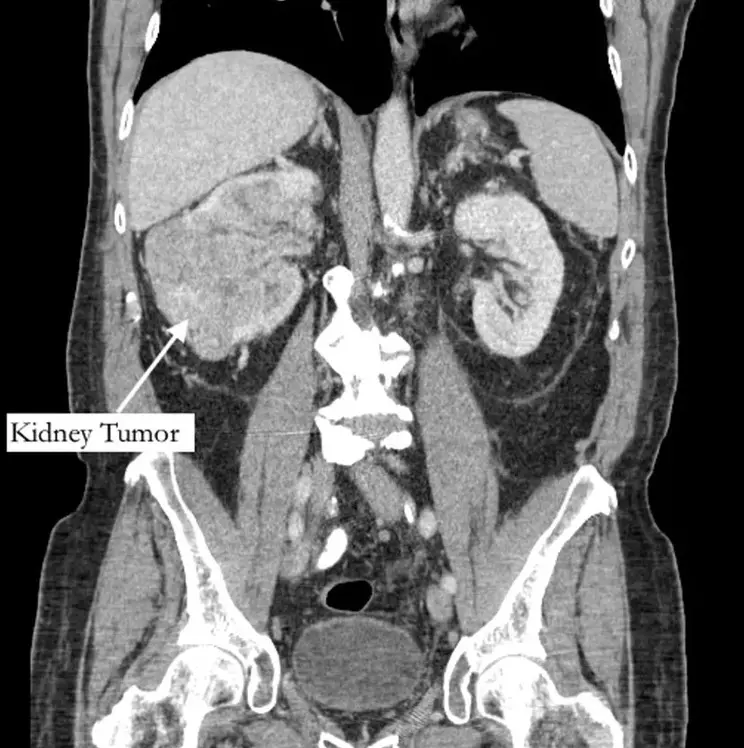

Imagem de um câncer

Legenda: Câncer foi descoberto após uma consulta de uma dor no pé

Foto: Divulgação/Northwell Health

Foi durante uma consulta por dor em dedão do pé direito que o aposentado Richard Bernstein, 42 anos, descobriu um câncer terminal. O caso aconteceu nos Estados Unidos, após o homem receber o diagnóstico de tumor no rim e de um trombo tumoral. As informações são do g1

Com a intensificação dos sintomas, um dos médicos solicitou um exame abdominal. Em março deste ano, ele já sentia dor no tornozelo e sua perna inchou. O exame revelou o tumor, que cresceu na veia renal e preenchia a veia cava.